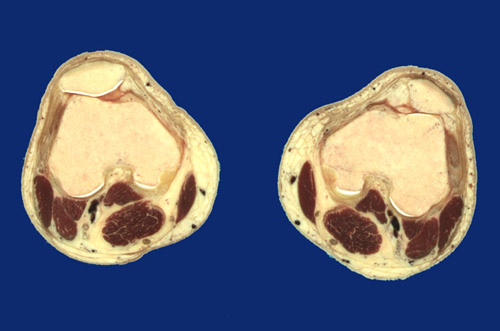

Identify the following regions in the image above: Popliteal vessels - Tibial nerve - Common peroneal nerve - Patella - Patellar groove - Synovial space - Articular cartilage - Sartorius - Gracilis tendon - Semitendinosus tendon - Semimembranosus - Gastrocnemius, medial head - Gastrocnemius, lateral head - Plantaris - Biceps femoris - Femur